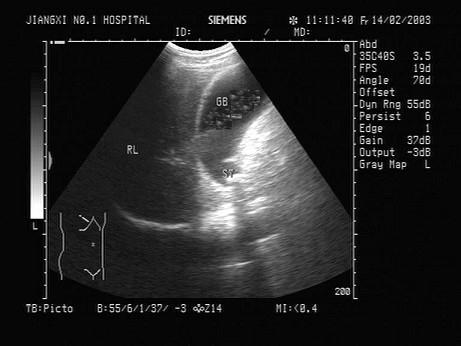

问题 女,39岁,上腹部经常疼痛数年,加重3天,低烧,结合超声声像图,诊断为?(?)

选项 A.胆囊结石并急性化脓性胆囊炎 B.胆囊息肉 C.胆囊结石 D.胆囊腺瘤 E.胆囊癌

答案 A